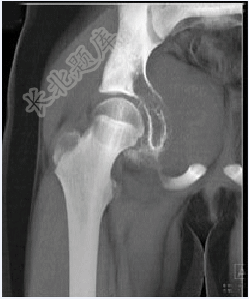

- 单项选择题男,15岁,右髋部疼痛、红肿,有压痛,皮温增高,结合图像,最可能的诊断是( )

A、Ewing肉瘤

B、急性骨髓炎

C、转移性神经母细胞瘤

D、骨肉瘤

E、骨结核